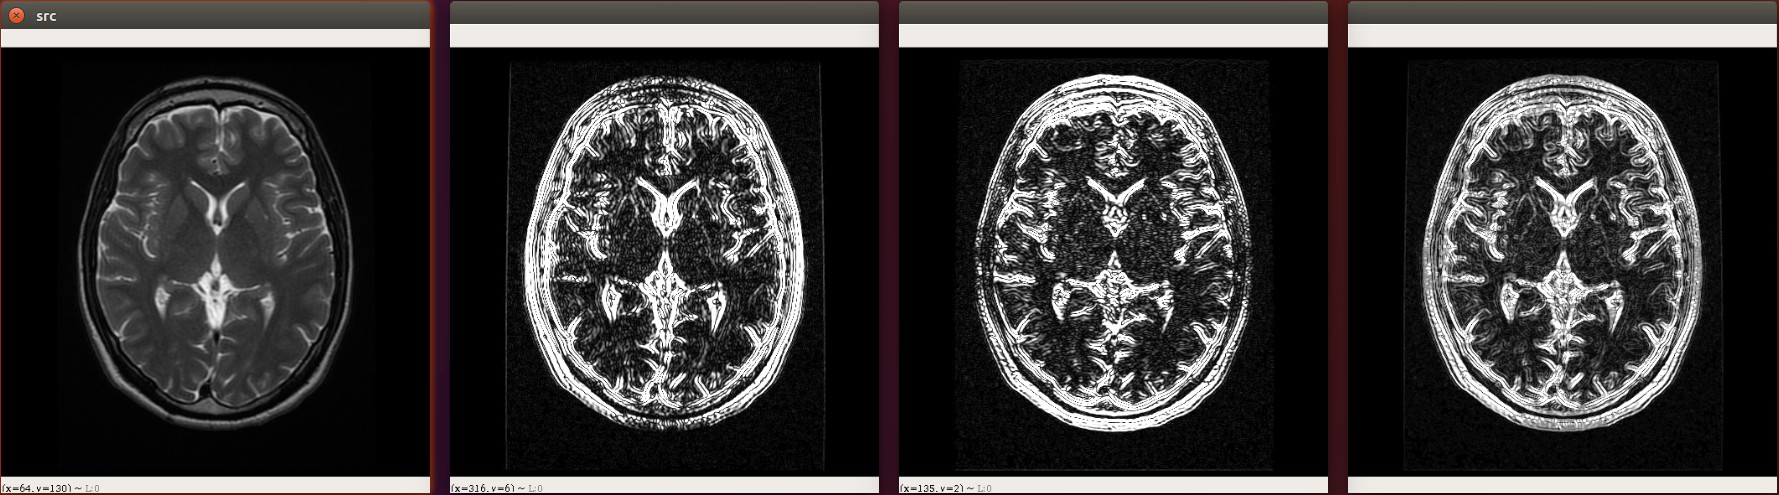

Sobel算子是像素图像边缘检测中最重要的算子之一,在机器学习、数字媒体、计算机视觉等信息科技领域起着举足轻重的作用。在技术上,它是一个离散的一阶差分算子,用来计算图像亮度函数的一阶梯度之近似值。在图像的任何一点使用此算子,将会产生该点对应的梯度矢量

import cv2 as cvimg = cv.imread("./assets/brain.jpg",cv.IMREAD_GRAYSCALE)

cv.imshow("src",img)# sobel算子 参数1:图像, 参数2:图像的深度 -1表示和原图相同, 参数3: x方向求导的阶数 参数4: y方向求导的阶数

x_sobel = cv.Sobel(img, cv.CV_32F, 1, 0)

# 将图像转成8位int

x_sobel = cv.convertScaleAbs(x_sobel)cv.imshow("x sobel",x_sobel)# sobel算子

y_sobel = cv.Sobel(img, cv.CV_16S, 0, 1)

# 将图像转成8位int

y_sobel = cv.convertScaleAbs(y_sobel)

cv.imshow("y_sobel",y_sobel)# 将x,y方向的内容叠加起来

x_y_sobel = cv.addWeighted(x_sobel, 0.5, y_sobel, 0.5,0)

cv.imshow("x,y sobel",x_y_sobel)cv.waitKey(0)

cv.destroyAllWindows()由于使用Sobel算子计算的时候有一些偏差, 所以opencv提供了sobel的升级版Scharr函数,计算比sobel更加精细.

下面是使用Scharr计算出来的边缘图像

import cv2 as cvimg = cv.imread("./assets/brain.jpg",cv.IMREAD_GRAYSCALE)

cv.imshow("src",img)# sobel算子

x_scharr = cv.Scharr(img, cv.CV_32F, 1, 0)

# 将图像转成8位int

x_scharr = cv.convertScaleAbs(x_scharr)

cv.imshow("x scharr",x_scharr)# # sobel算子

y_scharr = cv.Scharr(img, cv.CV_16S, 0, 1)

# 将图像转成8位int

y_scharr = cv.convertScaleAbs(y_scharr)

cv.imshow("y scharr",y_scharr)# 将x,y方向的内容叠加起来

xy_scharr = cv.addWeighted(x_scharr, 0.5, y_scharr, 0.5,0)

cv.imshow("x,y scharr",xy_scharr)cv.waitKey(0)

cv.destroyAllWindows()拉普拉斯算子¶